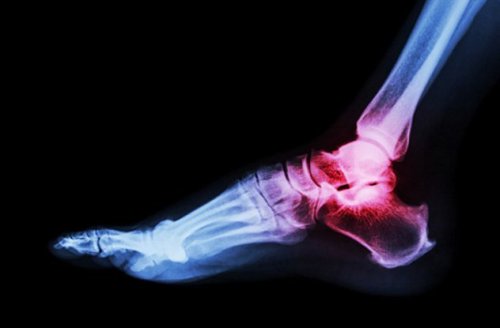

10. Сверхпрочные кости

Сломанная кость – это самое неприятное, что может с вами произойти, и это выбивает из колеи на недели и месяцы любого человека. Вопреки тому, что это самая прочная ткань в человеческом организме, кость однозначно не может считаться неуязвимой субстанцией. Разве что если у вас не обнаружат чрезвычайно редкую мутацию гена LRP5. Именно этот ген отвечает за плотность человеческих костей. Исследователи давно знали, что мутации LRP5 могут привести к формированию менее плотных и более хрупких костей, а также к развитию остеопороза. Но то, что могут иметь место и противоположные эффекты, было обнаружено совсем недавно.

Так у семьи из Коннектикута выявили невероятную мутацию гена LRP5, приведшую к такой прочности костей, что они практически не могут сломаться в тех обстоятельствах, когда кость любого другого человека уже бы по меньшей мере хрустнула. Естественно, никто из этой семьи никогда не ломал кости. Сконцентрированная в позвоночнике, черепе и тазобедренном отделе, эта увеличенная сила практически сделала из этой удачливой семьи людей с самым прочным скелетом в мире.

Исследователи полагают, что мутация провоцирует слишком много сигналов для роста костей, что приводит к повышенной плотности этих тканей. Чем не суперсила? Есть надежда, что однажды человечество научится контролировать эту форму мутации, и сможет побороть все заболевания костей.